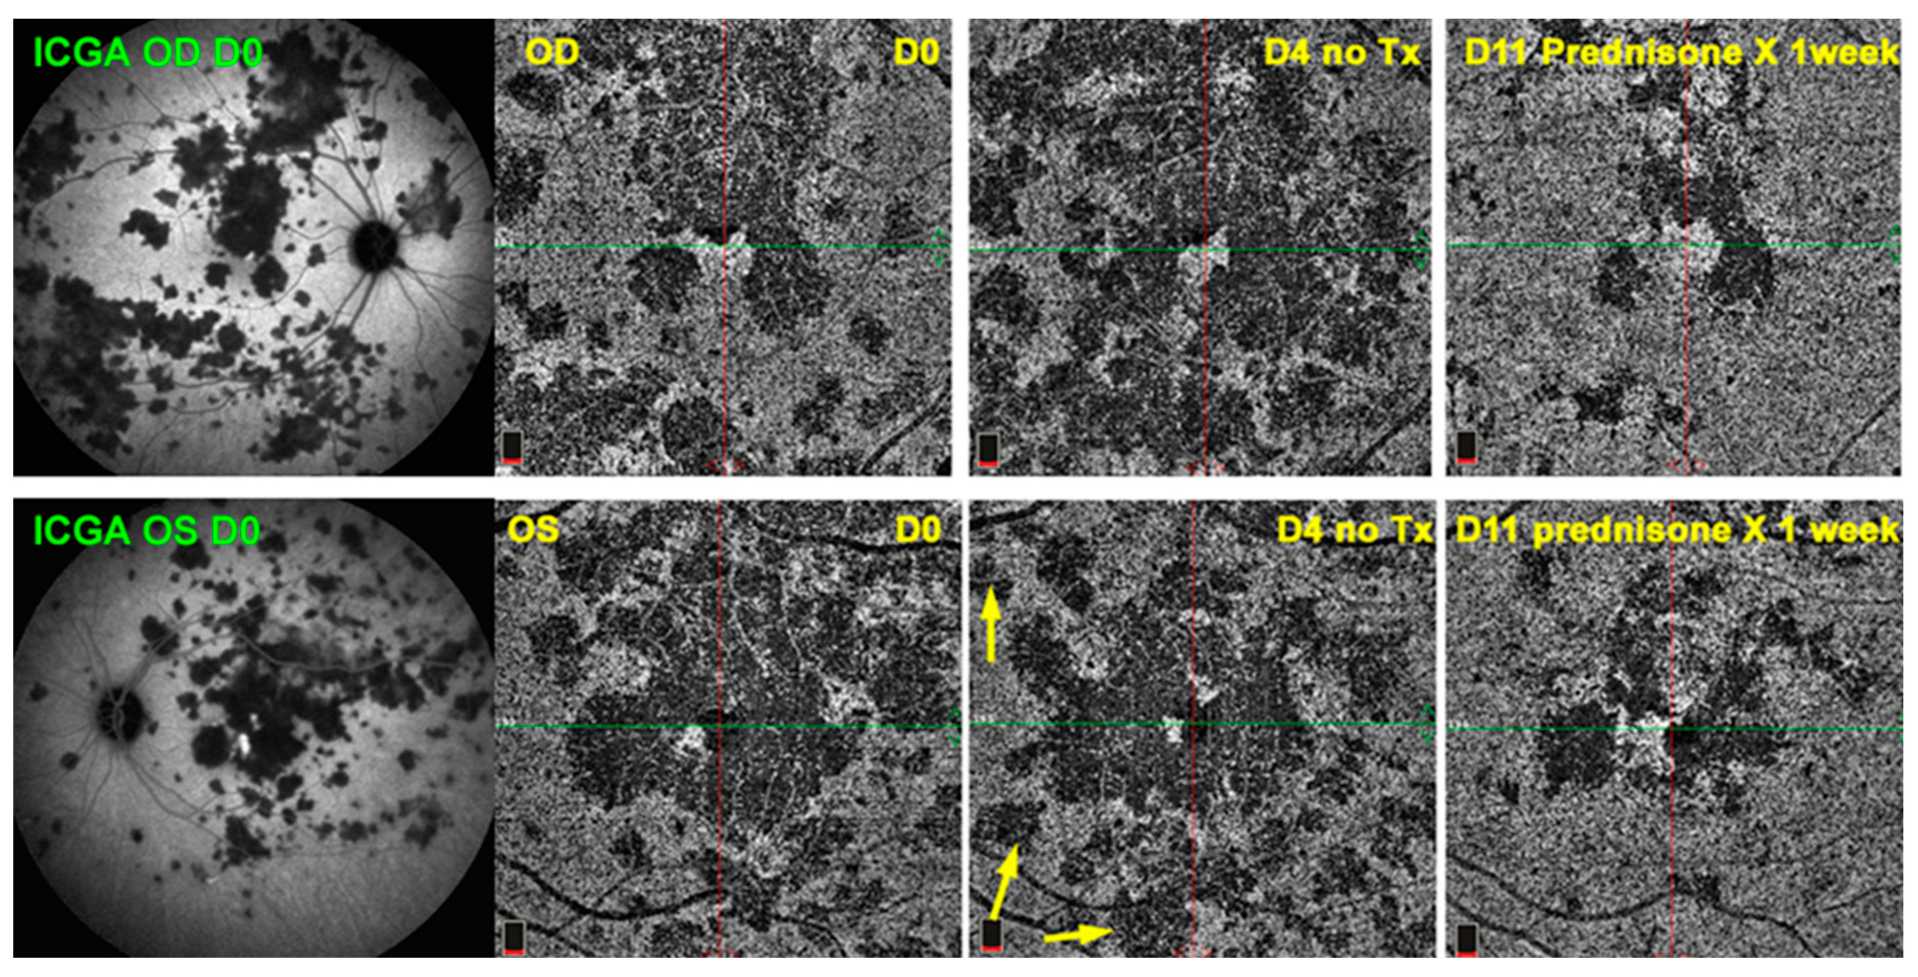

Figure 3. OCT-A follow-up of APMPPE. Example of practical usefulness of OCT-A in a patient with APMPPE (same patient as Figure 1). At presentation, ICGA frames clearly establish the global involvement of the fundus. To monitor the evolution of lesions and the impact of therapy, OCT-A allowed a close follow-up, although only of the central lesions (6 frames to the right). Yellow arrows show new areas of drop-out before regression of lesions following introduction of corticosteroids (frames at the extreme right).

4.4. Significant Contribution of OCT-A to Uveitis

There is no doubt that OCT-A represents significant progress in the appraisal of uveitis, as evidenced by the many research articles published since the method became available. We will refrain from citing again what has been extensively and repeatedly described. Many of these studies report new data which is still to be standardized in order to possibly be applied to everyday routine practice. Furthermore, the experiments were often performed on research instruments not readily available to general clinicians. We will, therefore, focus on the major intakes immediately beneficial for the practitioner in the daily management of patients. When investigating this point, we reviewed the utility of OCT-A in a specific center that uses a routinely available OCT-A instrument and evaluated, using pioneering pragmatism, the situations in which OCT-A provided further determining information to dye angiography, OCT, EDI-OCT and BAF data. Additionally, practical use reported in the literature was also considered. As a general rule, OCT-A was performed in most patients consulting for uveitis at presentation and for follow-up in the center. Within the 217 new uveitis cases seen from 2018 to 2022 in this center, 146 were examined with an Optovue instrument and 46 posterior uveitis cases were analyzed. Rare were the cases for which OCT-A was of crucial additional utility in the practical management of patients, so they will not be individually described hereafter. It did not provide diagnostic help in any patient after multimodal imaging was performed. It was useful for follow-up in two cases of APMPPE, showing the evolution of choriocapillary drop-out without the need to repeat ICGA (Figure 3). In five cases of inflammatory CNV due to MFC and APMPPE, it also helped with monitoring the evolution during treatment and allowed the researchers to reduce the number of dye angiographies performed.

The main situations where OCT-A was of determining utility in everyday practice from the literature were the rare inability to use fluorescein dye and the even rarer inability to use ICG because of allergic reactions. OCT-A was shown to be useful and to help in the detection of CNV, such as in MFC/PIC and other choriocapillaritis entities as well as its follow-up during treatment, but none of the articles recommended it for exclusive use. [31] One article clearly stated that OCT-A was not sufficient to replace dye angiography [39], and two articles indicated that OCT-A was unable to distinguish active from inactive CNV [37,38]. In predominantly retinal diseases, such as Behçet’s uveitis, OCT-A cannot be considered as essential in the diagnosis. However, analysis of macular microcirculation and its monitoring have shown to be useful to the clinician at times, although no standardization has been put forward so far [50]. The most useful application of OCT-A was for the group of choriocapillaritis diseases, including APMPPE, MFC and SC, and its utility resided mainly in the close follow-up it allowed, as no dye injection was needed [51] (Figure 3). As far as MEWDS is concerned, OCT-A was useless, as end-capillary low flow circulation is not identified by OCT-A. This was the origin of the erroneous thinking that there was an absence of choriocapillaris non-perfusion and, thus, an alleged intact choriocapillaris, as well as that MEWDS was supposedly a primary photoreceptoritis [52]. Although it was not included in our search terms, when trying to establish the essential, practical contributions of OCT-A, the article of Abucham-Neto et al. should be cited [53]. These authors indicate that OCT-A may better identify new vessels obscured by retinal hemorrhage, early peripapillary neovascular proliferation and telangiectasias. In this article, they also wrote “OCT-A was not able to detect clear signs of active inflammation around the affected vessels”.